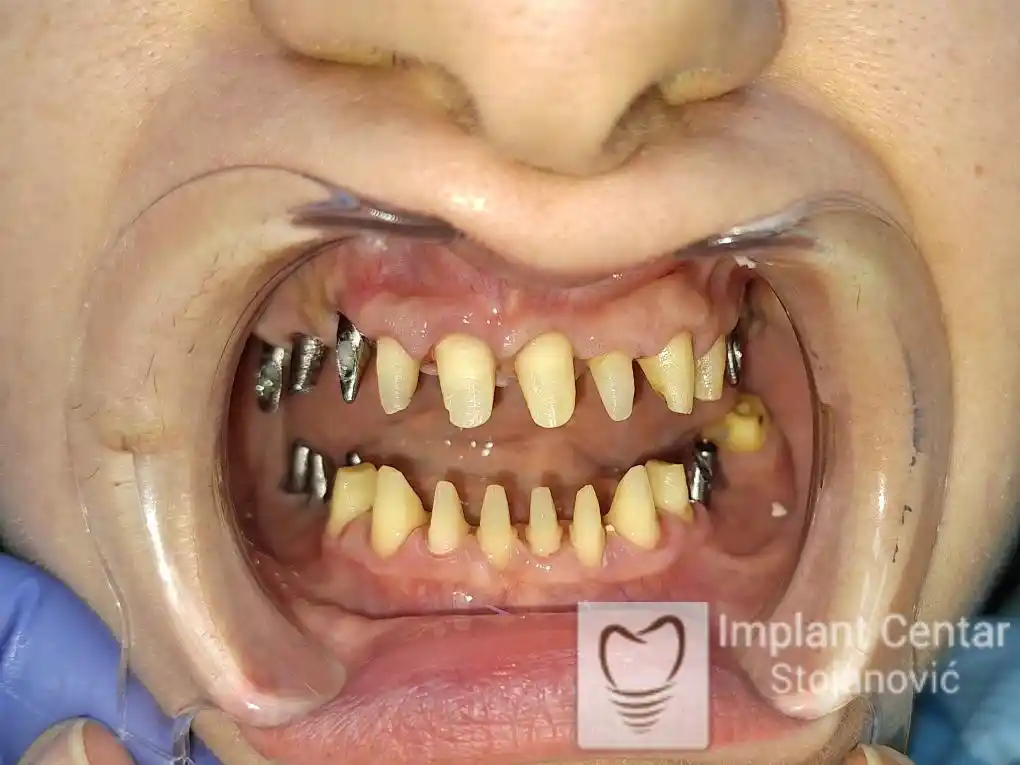

Pacijent sa rascepom usne, nepca i alveolarnog grebena uspešno je rehabilitovan fiksnim protetskim radom na implantatima. Pre dolaska u našu ordinaciju, pacijent je u gornjoj vilici nosio totalnu protezu preko preostalih zuba, dok je u donjoj vilici bio zbrinut parcijalnom mobilnom protezom. Tokom višegodišnje potrage za adekvatnim rešenjem, pacijent nije uspeo da pronađe zadovoljavajuću terapijsku opciju ni u zemlji ni u inostranstvu.

Nakon detaljnog kliničkog pregleda i analize radioloških snimaka, izrađen je sveobuhvatan plan terapije sa ciljem uklanjanja mobilnih proteza i postizanja maksimalne funkcionalne i estetske rehabilitacije. Zbog loše biološke vrednosti preostalih zuba, doneta je odluka o njihovom vađenju i ugradnji dentalnih implantata.

Na slikama 1, 2, 3 , 4  i  5 prikazan je izgled pacijenta pre početka terapije. Nakon detaljne kliničke i radiološke analize, doneta je odluka o vađenju zuba loše biološke vrednosti, dok su bezuba polja sanirana ugradnjom dentalnih implantata.